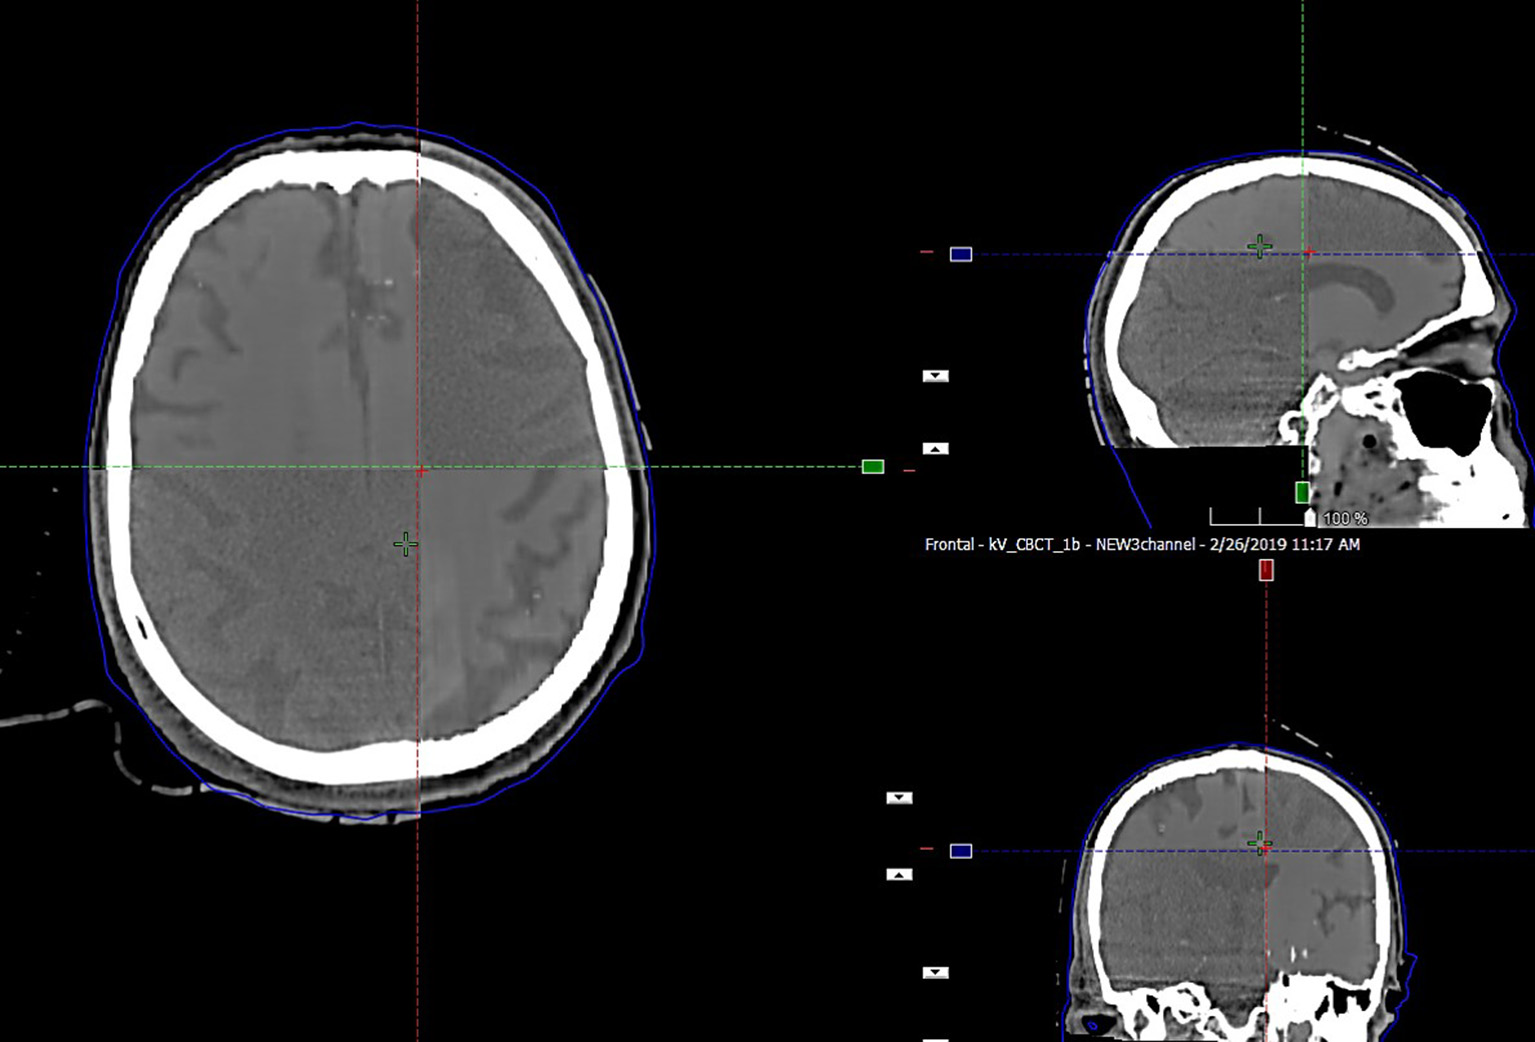

The preservation of major soft tissue interfaces is demonstrated in example images in Figure 4, which further shows support for soft tissue-based alignment between MRCT and CBCT. The MAE for the 13 test patients is reported in Table 1. The MAE for all voxels ranged from 58.1–118.1 HU with mean 81.0 HU and standard deviation 14.6 HU. Error values for each of the 3 channels are reported in Table 1. Mean MAE values for air, tissue and bone were 234, 22, and 193 HU, respectively.

FIGURE 4

www.frontiersin.org

Figure 4. Split window display of MRCT aligned with CBCT for an example patient, demonstrating the preservation of dominant soft tissue interfaces such as major sulci and ventricles as seen in axial, coronal, and sagittal cross sections through the image volumes.

Alignment results from CT to CBCT as well as corresponding MRCT-CBCT alignment showed a mean difference of −0.1 (σ 0.2) mm, −0.1 (σ 0.3) mm, and −0.2 (σ 0.3) mm about the left-right, anterior-posterior and cranial-caudal axes, respectively. The range of differences was (−0.3, 0.4), (−0.4, 0.3), and (−0.7, 0.2) mm about the same axes.